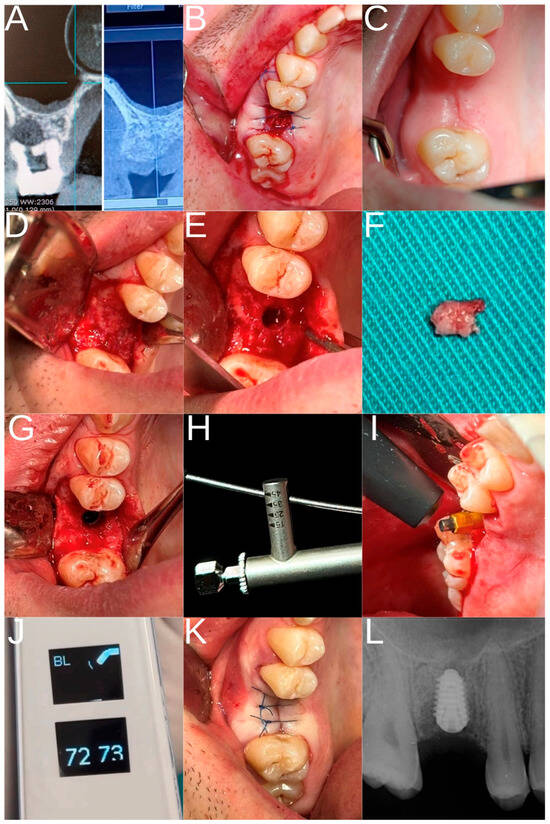

2.3. Study Groups and Surgical Procedure

- Control group: patients who had undergone extraction of the maxillary first molar at least eight months earlier, allowing spontaneous alveolar ridge healing and implant placement.

- Experimental group: patients who had undergone extraction of the maxillary first molar followed by ARP with HSCC and implant placement.